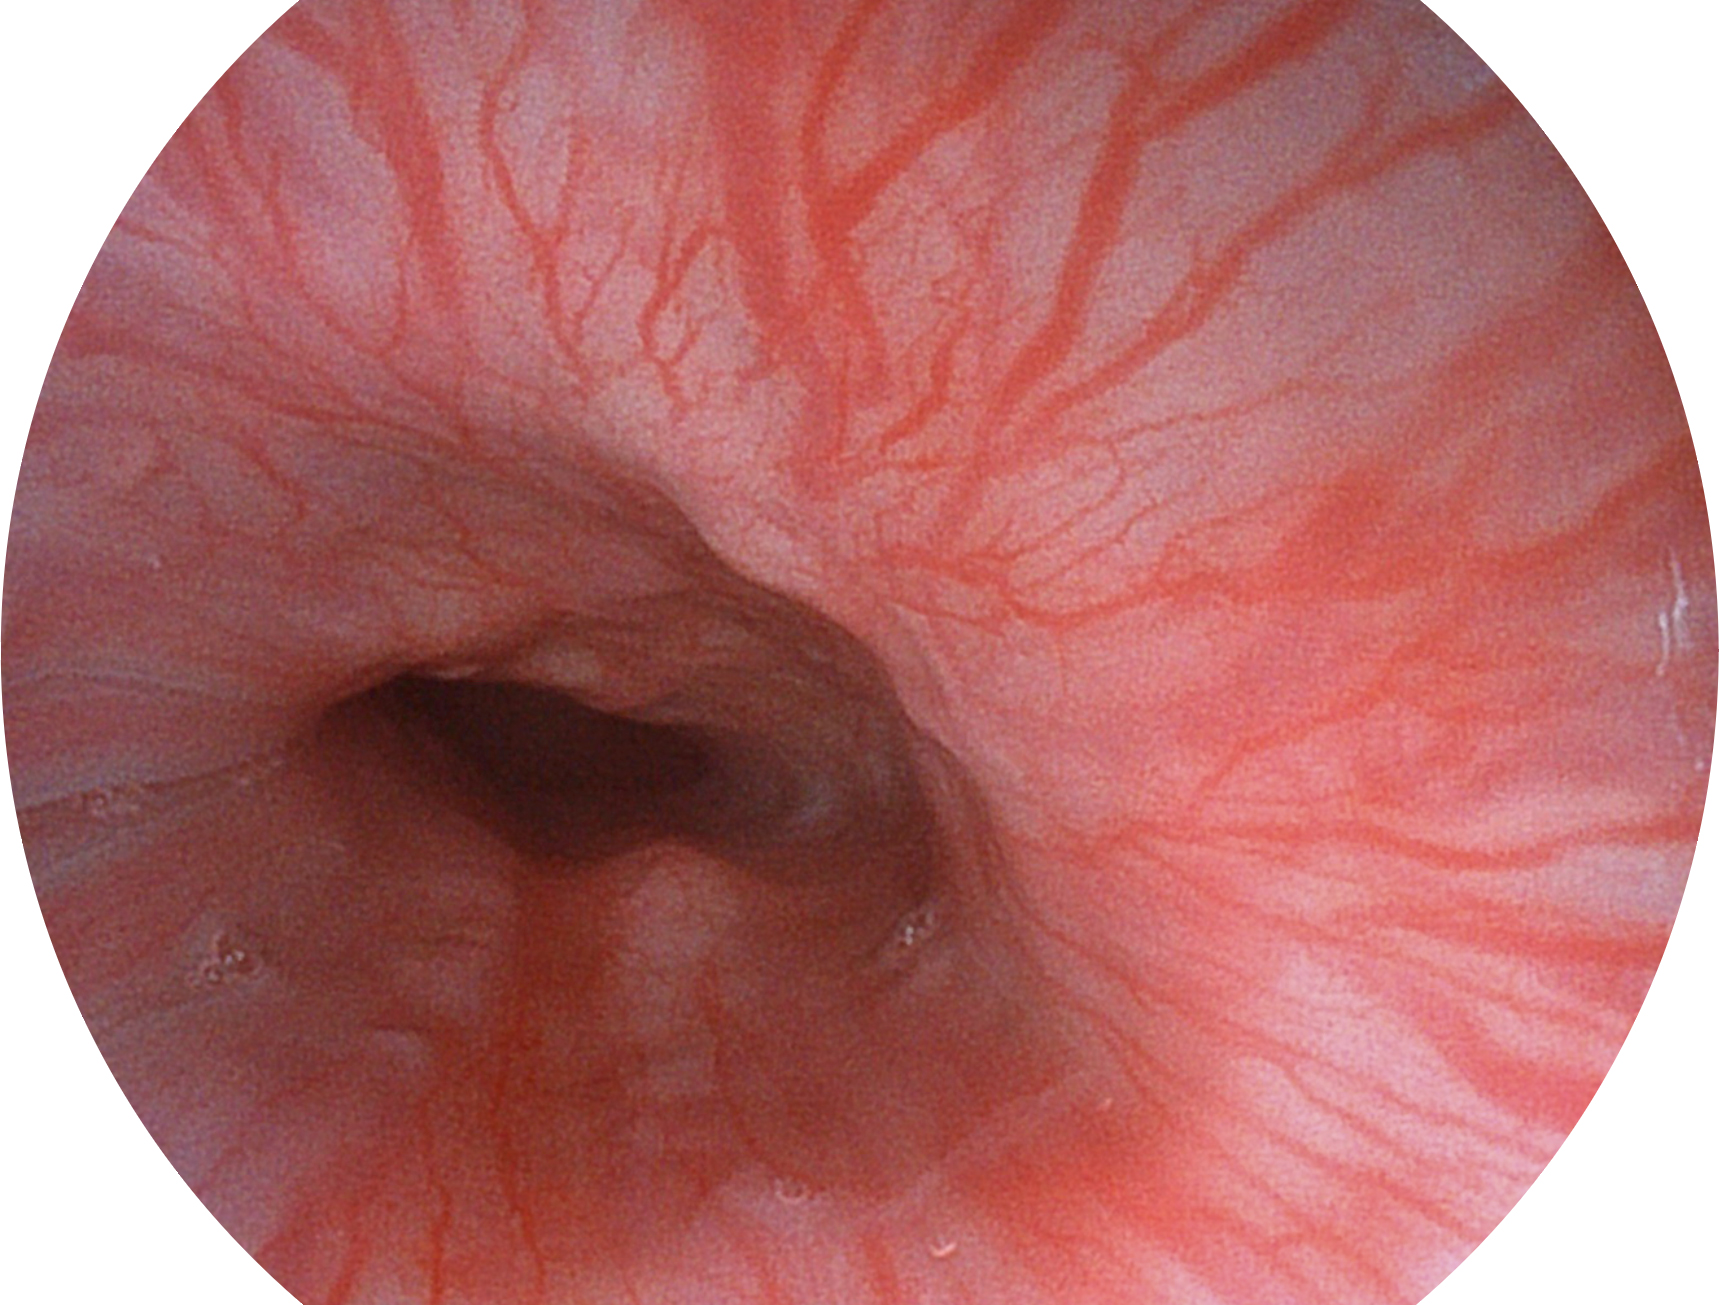

• 白光圖像 VIST圖像

• 白光圖像 SFI圖像